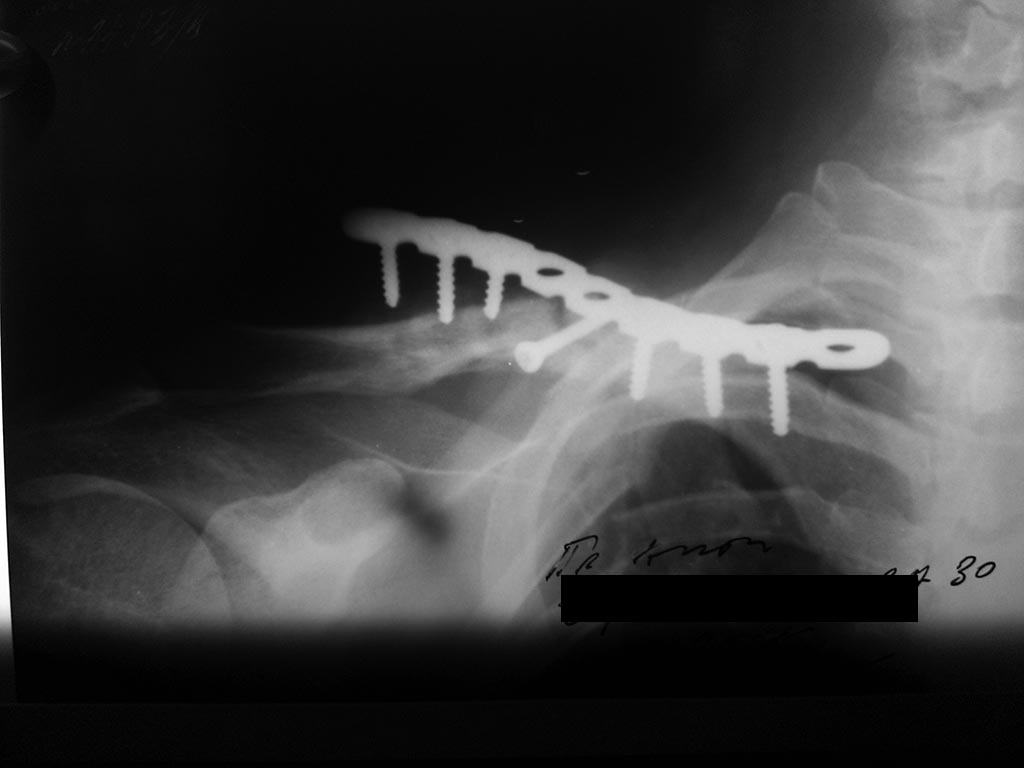

Пациент, 30 лет оперирован пластиной и винтами

Перелом на момент операции свежий, время операции - начало февраля 2015. Через 1,5 мес на контрольном снимке стояние пластины удовлетворительное.

Еще через месяц - диастаз дистального конца пластины и дистального отломка.

Важно: больной не соблюдал режим, через 2 недели от момента операции начал движения рукой.